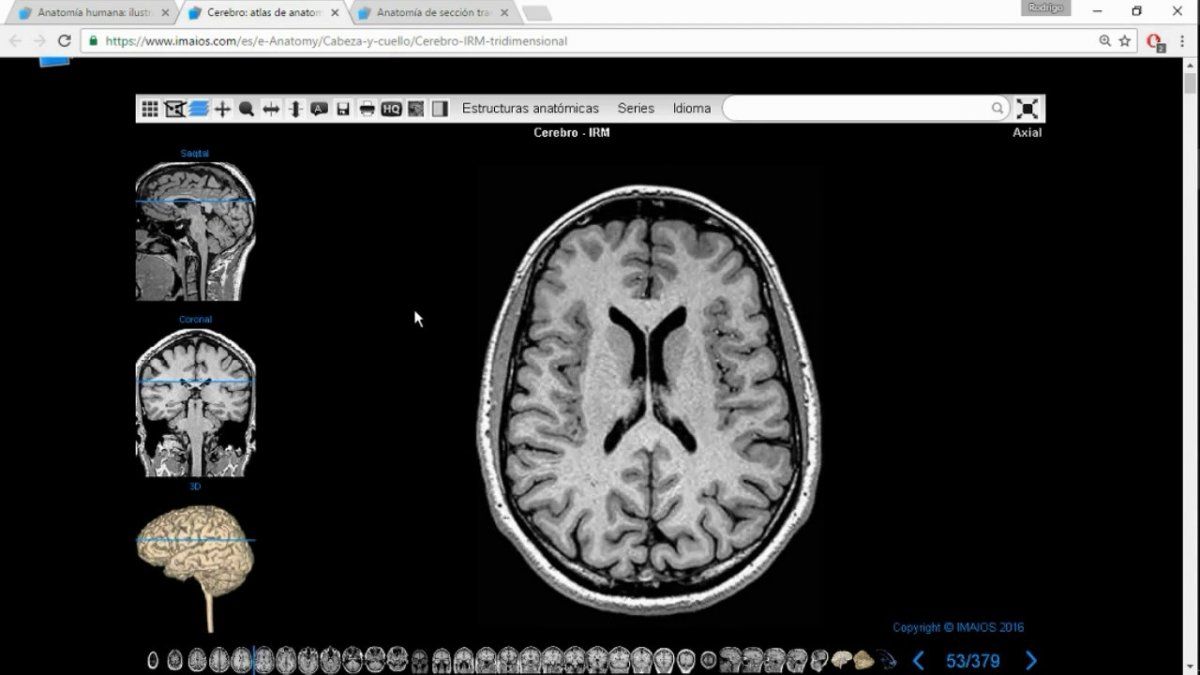

Para llevar a cabo su investigación, los científicos estudiaron los datos del Biobanco del Reino Unido, que cuenta con unas 40.000 tomografías por resonancia magnética que ciudadanos se hicieron antes del inicio de la pandemia. Entre los pacientes, se seleccionaron 782 personas, de las 394 enfermaron de covid-19 y 388 tuvieron resultados negativos. Todos los participantes se hicieron una imagen por resonancia magnética repetida y los investigadores compararon sus resultados con los anteriores.

El análisis de los datos del grupo que padeció covid-19 en algún momento mostró una pérdida "significativa" de materia gris en regiones del cerebro relacionadas con el olfato y el gusto: el giro parahipocampal izquierdo, la corteza orbitofrontal izquierda y la ínsula izquierda. Estos cambios no se observaron en el grupo que no se infectaron.